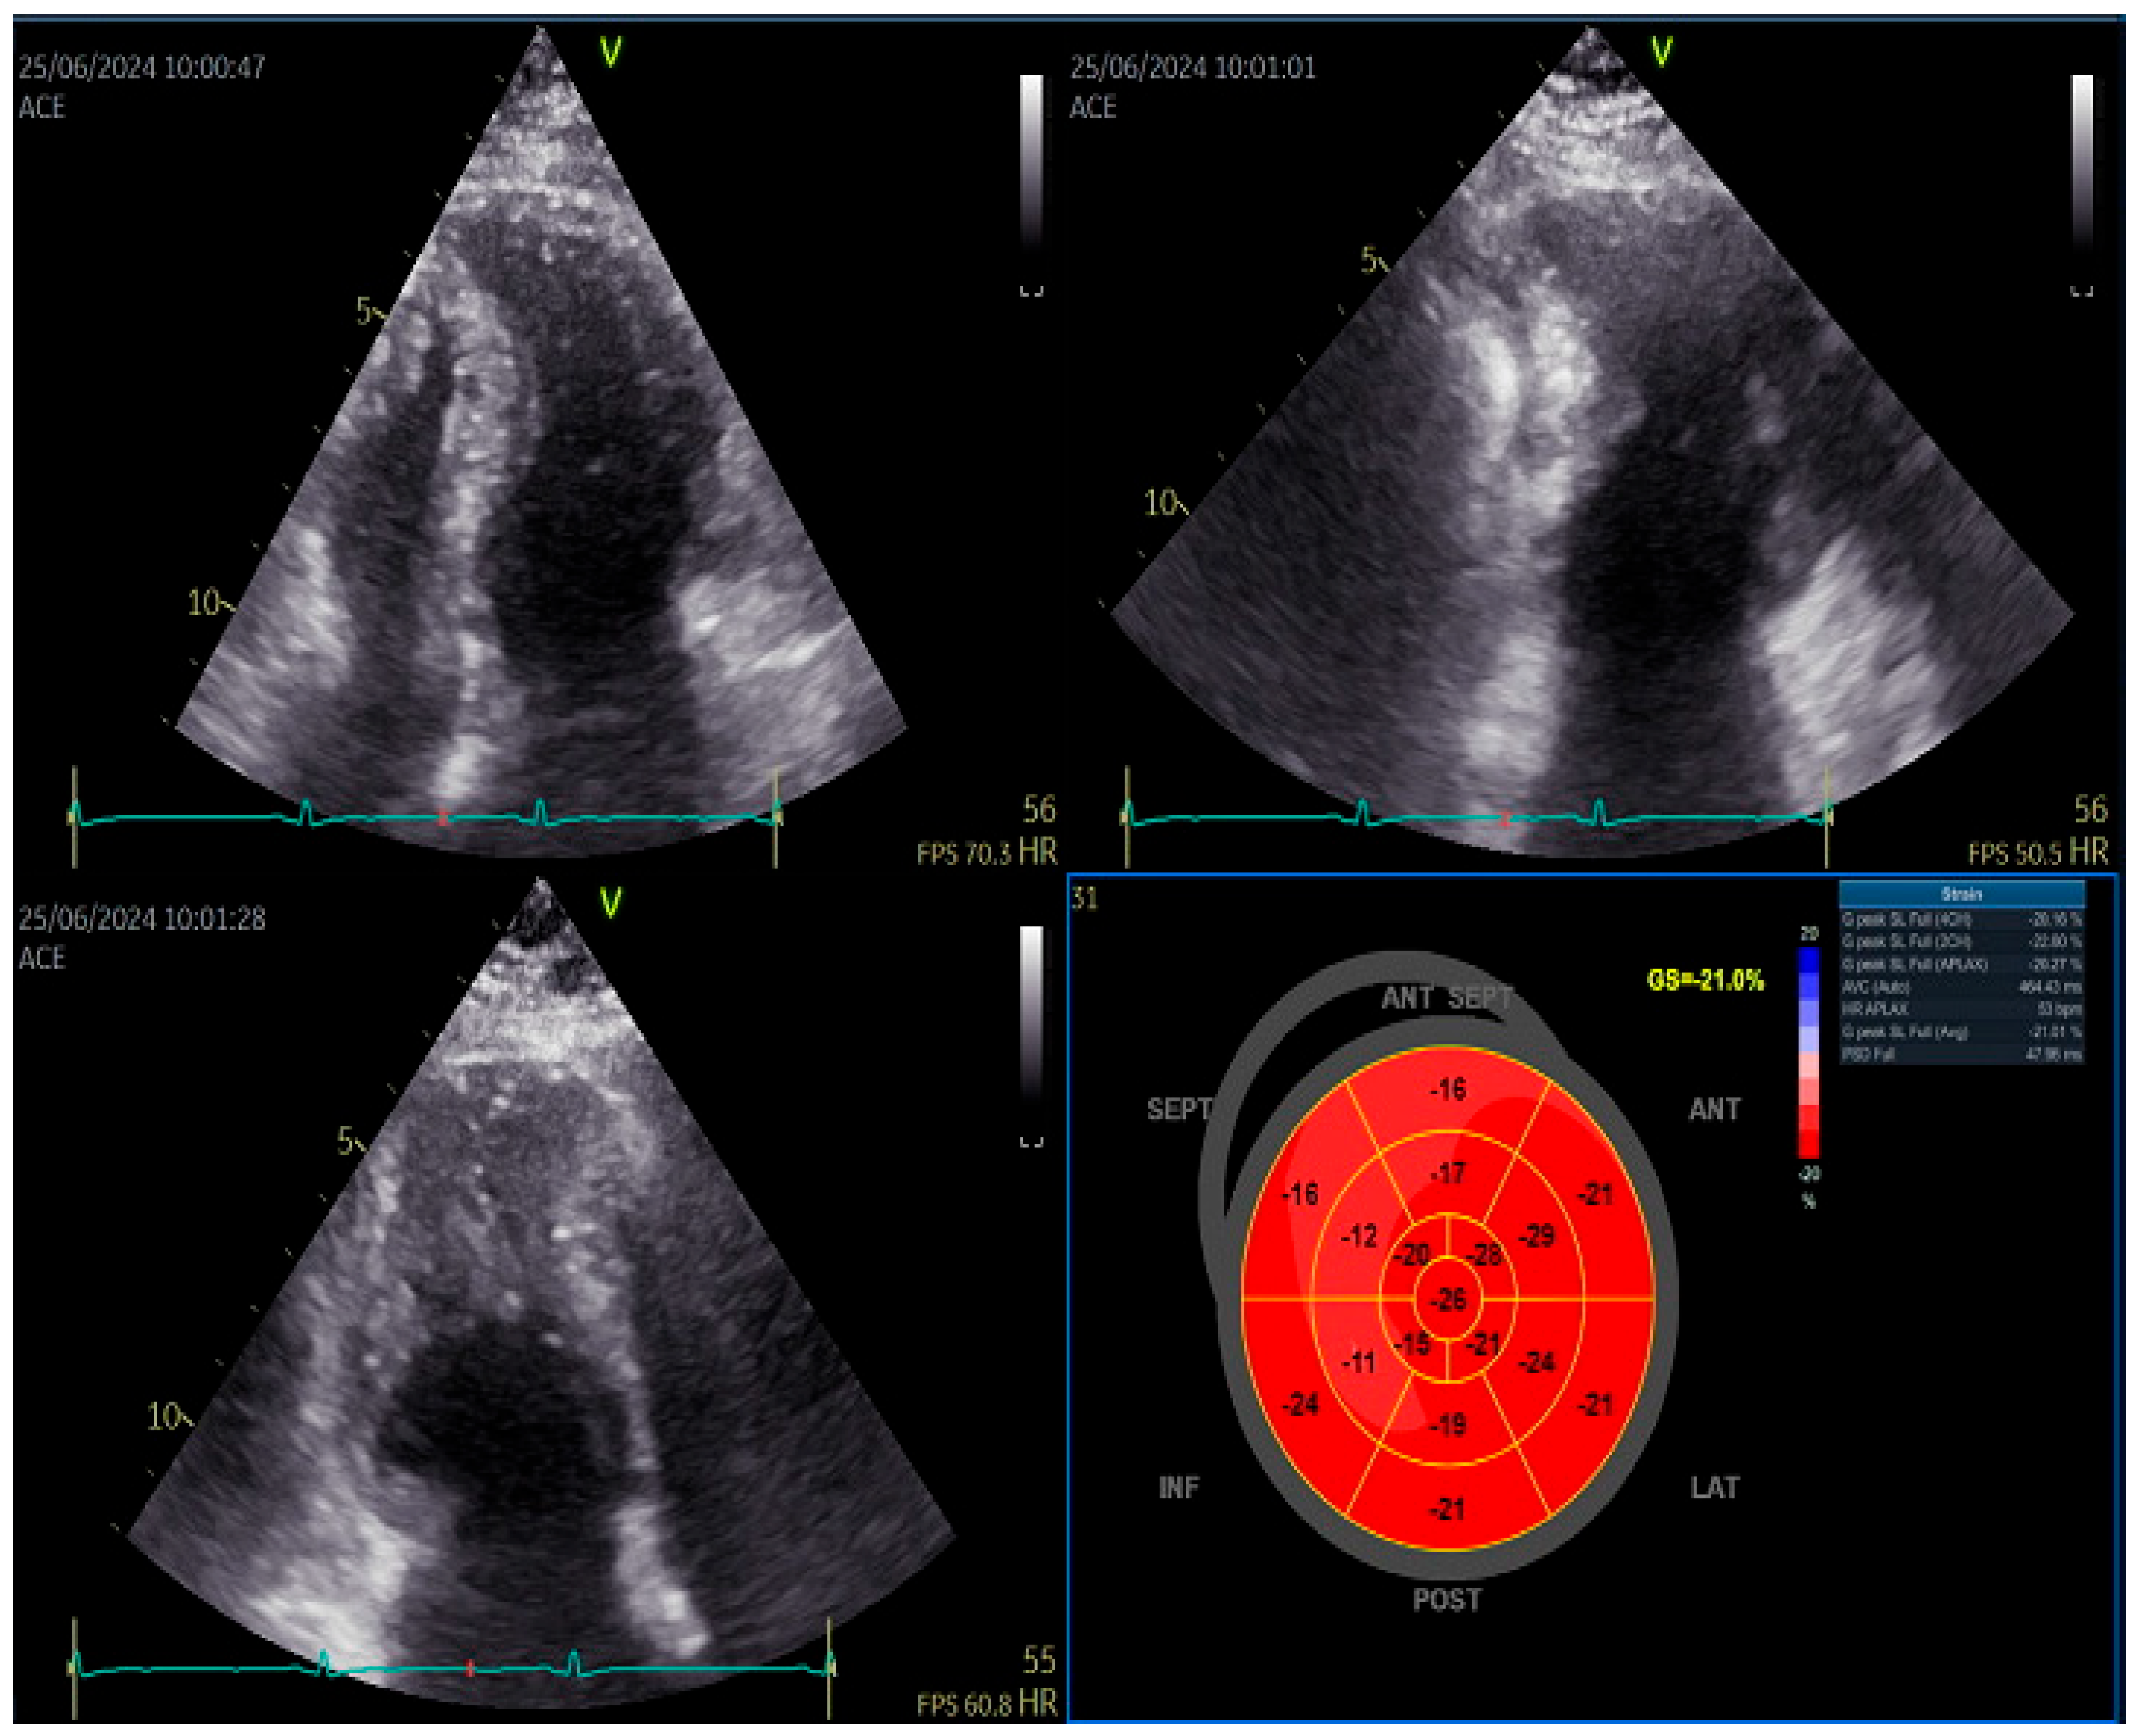

Transthoracic echocardiography showed normal diameters and volumes of the left ventricle. Interventricular wall thickness (IVWT) was within the normal ranges, respectively 8 mm. Transmitral Doppler showed a restrictive filling pattern with elevated E/A ratio and shortened deceleration time, consistent with impaired diastolic compliance. Extreme left atrium (LA) dilatation was observed, with the volume of 134 mL/m2. (Figure 1)

Speckle tracking echocardiography revealed normal GLS and slightly decreased septal longitudinal strain but still within the normal ranges [6]. Left atrium strain showed reduced reservoir function (27%).

Figure 2. Left ventricular speckle tracking echocardiography showing slightly reduced septal longitudinal strain.

Figure 1. Apical four chamber image showing severe dilatation of the left atrium.